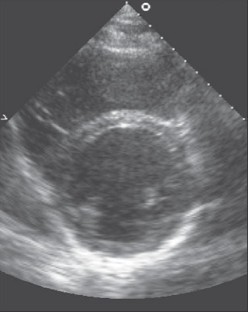

Cardiac remodelling is commonly defined as a physiological or pathological state that may occur after conditions such as myocardial infarction, pressure overload, idiopathic dilated cardiomyopathy or volume overload. When training excessively, the heart develops several myocardial adaptations causing a physiological state of cardiac remodelling. These morphological changes depend on the kind of training and are clinically characterised by modifications in cardiac size and shape due to increased load. Several studies have investigated morphological differences in the athlete’s heart between athletes performing strength training and athletes performing endurance training. Endurance training is associated with an increased cardiac output and volume load on the left and right ventricles, causing the endurance-trained heart to generate a mild to moderate dilatation of the left ventricle combined with a mild to moderate increase in left ventricular wall thickness. Strength training is characterised by an elevation of both systolic and diastolic blood pressure. This pressure overload causes an increase in left ventricular wall thickness. This may or may not be accompanied by a slight raise in the left ventricular volume. However, the development of an endurancetrained heart and a strength-trained heart should not be considered an absolute concept. Both forms of training cause specific morphological changes in the heart, dependent on the type of sport. (Neth Heart J 2008;16:129-33.)